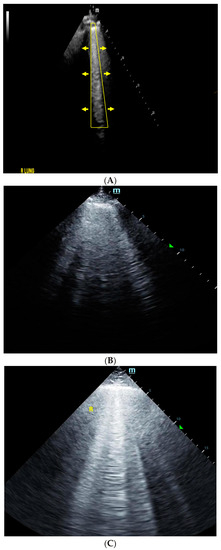

4. Lung Ultrasound

5. Inferior Vena Cava Ultrasound

6. Venous Excess Ultrasound Score